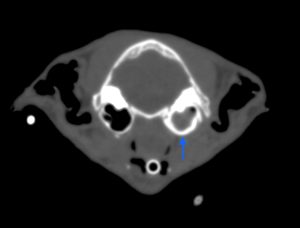

CT検査では、鼻咽頭に左の耳管から続く腫瘤(オレンジ丸)がほぼ完全に鼻咽頭を閉塞していました。また、左の中耳にも病変(青矢印)を認めました。